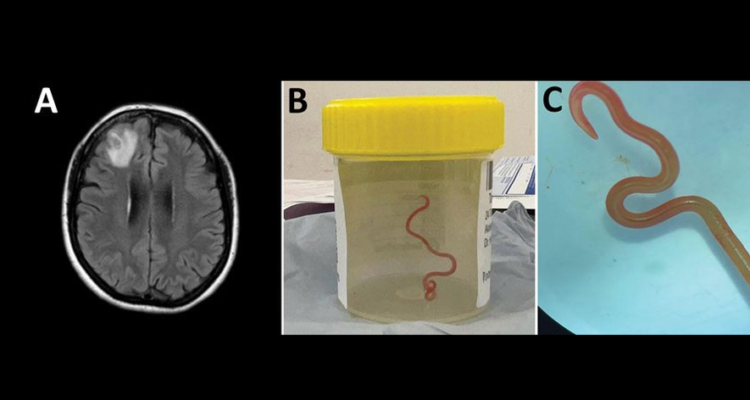

Le ver, appelé «Ophidascaris robertsi» mesurait 8 centimètres de long.

Le neurochirurgien Hari Priya Band a dépisté et retiré le ver de 8 centimètres, vivant dans le cerveau de l’une de ses patientes. Originaire du sud-est de l’Australie, la femme avait souffert d’abord de douleurs abdominales, de diarrhée puis d’une toux sèche, de sueurs nocturnes et de fièvre.

Un an après, la femme de 64 ans a développé une perte de mémoire et une dépression. Après une IRM du cerveau, une «anomalie nécessitant une intervention» a été révélée.

Le ver est un «Ophidascaris robertsi» déjà connu pour se nicher à l’intérieur des pythons mais c’est la première fois qu’elle est découverte chez l’Homme.